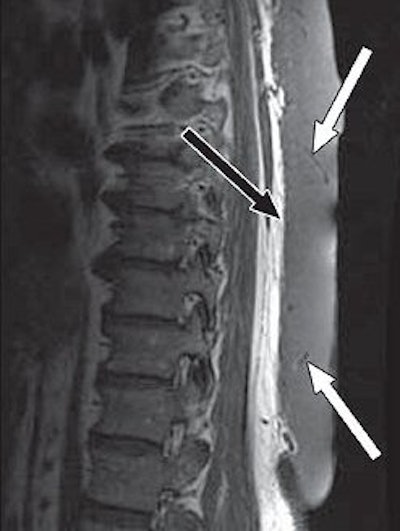

![]() |

| A 65-year-old man with plaque-like diffuse neurofibroma. Above, sagittal T1-weighted MR image (TR/TE, 500/16) shows thick plaque-like diffuse neurofibroma involving skin and subcutaneous tissues of back. Deep aspect (black arrow) of mass is well-defined, and deeper subcutaneous tissues are uninvolved. Small flow voids (white arrows) reflect prominent internal vascularity. Below, sagittal T2-weighted MR image (3,200/104) shows diffuse neurofibroma (white arrows) that is markedly hyperintense in relation to muscle (black arrow). |